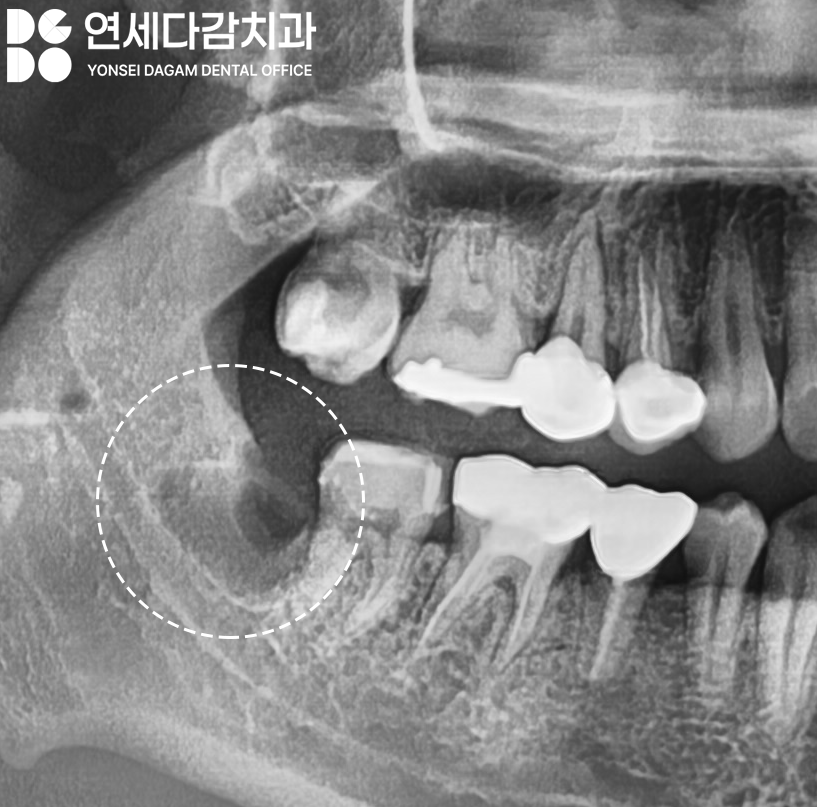

일반적으로 매복 사랑니가

존재한다면 누워있는 수평

형태일 때가 많습니다.

이때 대부분 인접치를 향해

기울어져 있을 때가 많은데,

간혹 치아의 머리 부분인 치관이

설측(혀 쪽)으로 향하고 있는

경우가 있습니다.

이런 상황에서는 발치 과정이

훨씬 까다로워집니다.

이러한 복잡한 케이스에서는

CT 촬영을 통해 3차원적인

구조 분석을 통해

안전한 발치 전략을

미리 수립하는 것이

필수 과정입니다.

수평으로 매복된 경우,

CT 분석 결과 하치조신경과

근접해 있는 경우가 많습니다.

이가 나온 부위는

점차 자연스럽게 치유되며,

12개월 이후 정기검진에는

뼈가 안정화되어

오금동 치과 에서 보여드린

X-ray 상에서 밀도가

높아진 것을 확인할 수 있습니다.